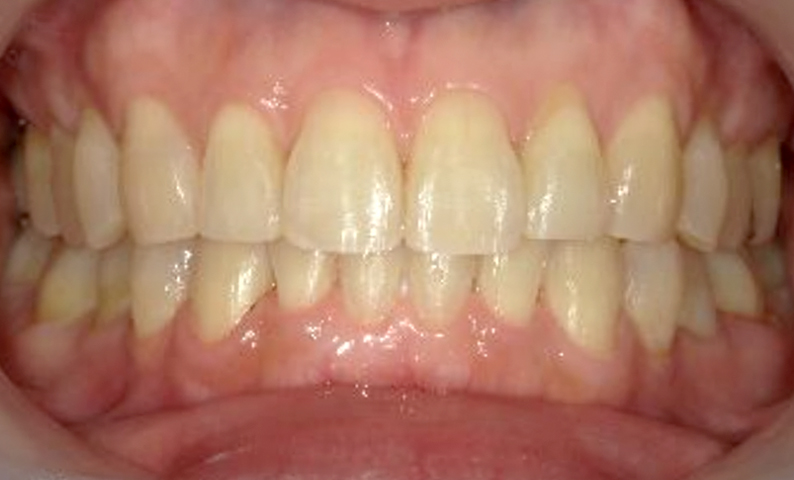

症例_030 上下顎の部分矯正

治療期間:12ヶ月金額:54万円+税女性八の字/V字型捻転歯前歯のガタガタ

| Before | After |

|---|---|

|